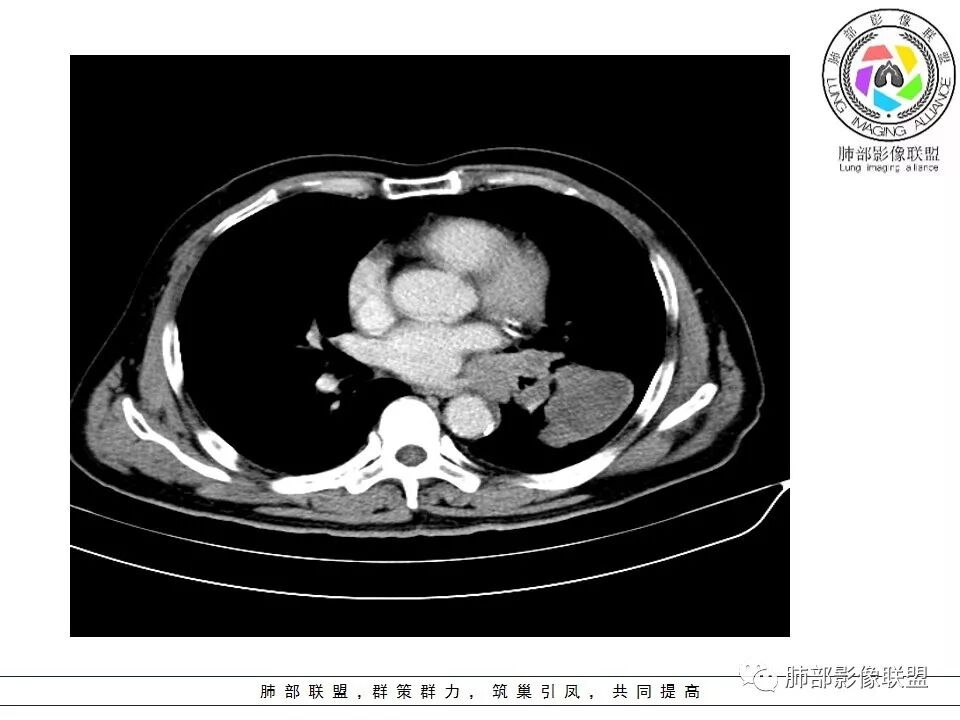

老年男性,症状轻。左肺下叶类圆形肿块,边界清楚,分叶不明显,其内无空泡征,边缘无毛刺及胸膜牵拉,远端无阻塞性肺炎。左肺门影增大。增强扫描左肺下叶肿块可疑轻度强化(无平扫对比),局部见小尾巴征。左肺门区见不规则形团块,似多个结节融合,肺动脉受压穿行于病灶中,形成冰冻肺门感觉,局部层面似见肺门区团块与左肺下叶肿块相连。综合考虑小细胞肺癌(SCLC)。

左肺门乱乱的,有血管受压表现,有支气管腔内占位表现,肺门淋巴结肿大肯定是有的;左肺下叶见一巨大包块,边缘光滑,内侧又一个切迹,考虑是病变受到了小叶间隔阻挡造成的其内部大部分不强化,但有局部一小片强化;壁不均匀环形强化,总体较薄;周围没有阻塞性肺炎,感染性病变应该是不考虑的,因为周围清楚,也没有感染的症状,还是考虑肿瘤性病变;关键是它边缘光滑,内部应该是坏死,但有强化提示坏死不彻底,这么大了,边缘恶性征象不明显,不符合腺癌,鳞癌呢也不太符合,阻塞性肺炎没有,坏死太明显了,这么大,边缘光滑,坏死明显,符合肉瘤和肉瘤样癌,不除外小细胞肺癌

南边:病灶分为两大块,外围囊实性大肿块,支气管关系不密切,内带多发淋巴结,侵犯支气管、肺血管,恶性没问题,按理间叶为主,或不典型的癌,这不是一个中央型的肺癌,是外朝内进展的,奇怪的是边界这么清楚光滑,一般癌肉瘤、肉瘤类多,其次才是癌,远端也没有阻塞,大方向是这样,恶性,间叶来源?或者混合,恶性程度较高,鉴别就是结核,因为结核是妖

2娘小崽大、淋巴及血行转移早、冰冻纵隔及肺门血管脂肪间隙消失

因为病灶侵袭力强,病灶易沿淋巴道、间质及心血管间隙等结构侵犯并密切挤压上述结构,常常能够观察到脂肪间隙消失。易于出现冰冻纵隔。原发灶与肺门转移灶可形成哑铃状外观,甚至转移灶体积大于周围原发灶,有人称之为“娘小崽大”。早期病灶有时很小甚或隐匿,仅能看到转移灶,或转移淋巴结与原发灶融合分界不清。病变向肺门延续的串珠样淋巴结转移也是SCLC的典型特点。

1.左肺下叶近肺门区肿块,肿块外围大,内带小,提示外围向中央生长,符合周围型SCLC沿支气管方向生长。

2.病灶边缘光滑,未见明显分叶、毛刺,符合神经内分泌癌、癌肉瘤及间叶来源肿瘤。

5.病灶内有血管走行,血管局部受压,但是强化考虑为乏血供,提示病灶内肺动脉并不是供血血管,只是病灶侵袭性强把血管包埋而已,为血管包埋征;血流面光滑,血管包埋符合SCLC。

6.左肺门淋巴结肿大,与病灶局部融合分界不清,呈冰冻肺门;而纵隔内未见肿大淋巴结,冰冻肺门符合SCLC,但是病灶主体那么大,纵隔内没有明显肿大淋巴结,不是很符合SCLC娘小崽大的特点。